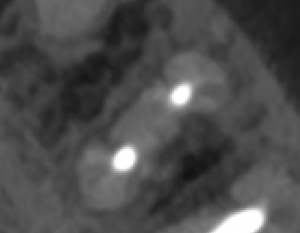

当該部位を2mm Osteotomyすると#19 MのApexが発見できそこを3mm切断するには頬舌径が6.2mm必要である。

当該部位をOsteotomyした。歯槽骨は2mm削合する必要がある。

Apexを3mm削除し取り除いた。

逆根管形成はMB-MLを往復しなければならないが、

間がかなり離れているので逆根管形成には時間がかかる。